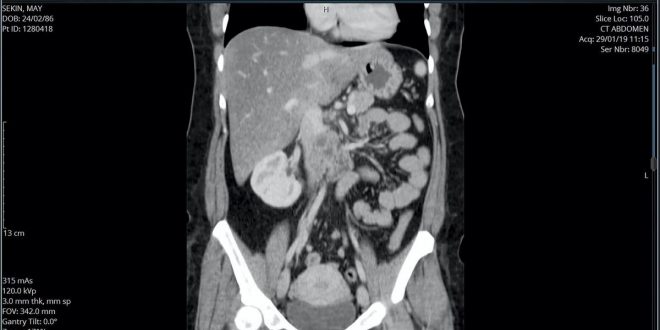

A woman who had a tumour the size of a grapefruit removed from one of her major veins has recovered from what doctors described as “one of the most complex cases they had ever seen”.

Over three months, X-rays and scans revealed that she had a massive and potentially life-threatening tumour that was pressing on her abdomen.

The malignant tumour was a cancerous growth called a leiomyosarcoma.

Ms Mohammed’s tumour, an extremely rare type of cancer that develops in the soft tissue of the body, grew in the muscle lining of her inferior vena cava – one of the body’s two main veins – that

runs along the spine and returns deoxygenated blood to the heart from the lower part of the body. “My husband and I and the entire family were in shock,” said the physical education teacher.

“The tumour was putting pressure on the pancreas and the duodenum [part of the small intestine] but after we got in there, we realised that the source was actually the inferior vena cava.